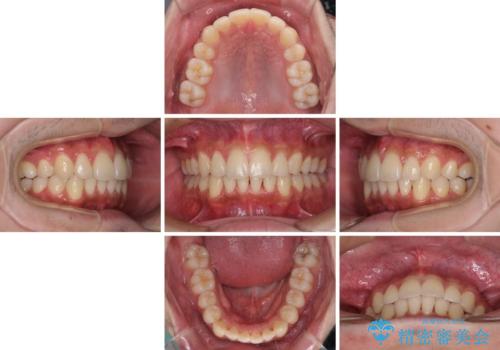

矯正治療の後戻りをインビザライン・ライトで解消

- 矯正治療の後戻りを気にして来院された患者様です。

後戻りは軽微であったので、インビザライン・ライトにより矯正治療を行うこととしました。

矯正治療後は、再度後戻りすることを極力回避するために、下顎前歯の舌側を細いワイヤーを用いて保定することとしました。